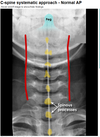

AXR: sentinel loop, pancreatic calcification